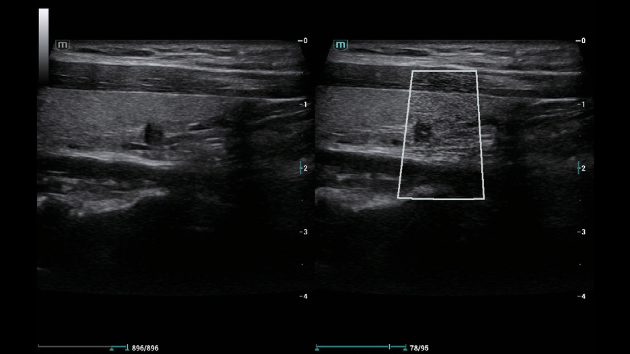

Solu??es abrangentes de imagens com tecnologia ZST+

A plataforma ZST+ ÃĐ uma inova??o extraordinÃĄria, representando a evolu??o do ultrassom. Transformando as mÃĐtricas de ultrassom: da forma??o convencional do feixe ao processamento baseado em dados de canais. Supera a limita??o de compensa??o tradicional entre resolu??o espacial, resolu??o temporal e uniformidade de tecido, oferecendo qualidade de imagem excepcional para solu??es de imagem infinitas com melhorias inigualÃĄveis.